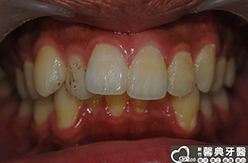

上、下顎前突,俗稱暴牙,由於上下前牙向前暴出,在外觀上容易產生牙齒外露的現象,雙唇較難自然閉合,嘴唇看也來也會比較厚。

患者︰趙同學,20多歲,學生。

主訴︰齒列不正,暴牙,不好看。

治療計劃︰上下顎齒列平整、後縮,重建正常咬合關係。

| ●治療前 | ●治療後 | |